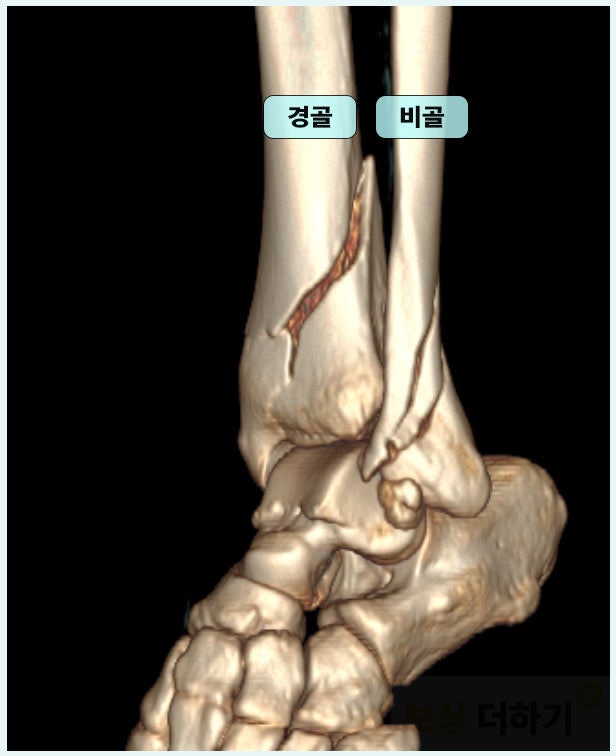

진단서의 질병분류기호에 s82320으로 표시되어 있는 분들이 계실 겁니다. 비골 골절(모든 부분)을 동반한 경골 하단의 골절 비골은 종아리 바깥쪽의 가늘고 긴 뼈, 경골은 종아리 안쪽의 굵고 무게를 많이 지지하는 뼈입니다. 아래 사진에서 볼 수 있는 것처럼 이 두 개의 뼈 하단이 모두 골절되었을 때 부여되는 코드입니다.

■ 내부 고정술 경골, 비골의 아랫부분은 발목을 접질렀을 때 힘을 집중적으로 받는 부위로 당시 심각한 골절이 발생하였고, 이에 따라 수술 치료가 필요했습니다.